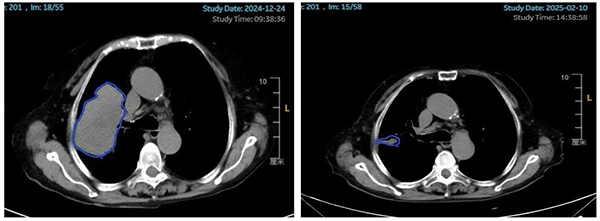

80歲的患者李女士(化名)2024年2月確診為右肺腺鱗癌,經(jīng)過靶向治療、化療后出現(xiàn)多次進(jìn)展。2024年12月24日查胸部CT提示右肺上葉病灶增大至95mm×64mm(圖1左側(cè)所示)?紤]腫瘤體積巨大,腫瘤內(nèi)部可能出現(xiàn)壞死、乏氧,常規(guī)放療難以取得理想的治療效果,并且大概率會對腫瘤周圍的心臟、肺、臂叢神經(jīng)等正常組織造成較大損傷,嚴(yán)重影響患者的生活質(zhì)量,腫瘤放療科副主任丁昕組織蔣愛軍主任醫(yī)師、李亮副主任物理師等團(tuán)隊成員進(jìn)行綜合評估和細(xì)致討論,決定采用空間分割放療技術(shù)。李女士整個療程接受了6次放療(常規(guī)放療一般至少需要30次),住院時間明顯縮短。治療結(jié)束后李女士自覺咳嗽癥狀明顯好轉(zhuǎn),1月后,2025年2月10日復(fù)查胸部CT提示右肺上葉的巨大腫瘤幾乎完全消失(圖1右側(cè)所示),取得了出乎意料的治療效果。

圖1.患者治療前后的影像對比(藍(lán)色標(biāo)記的為腫瘤部位)